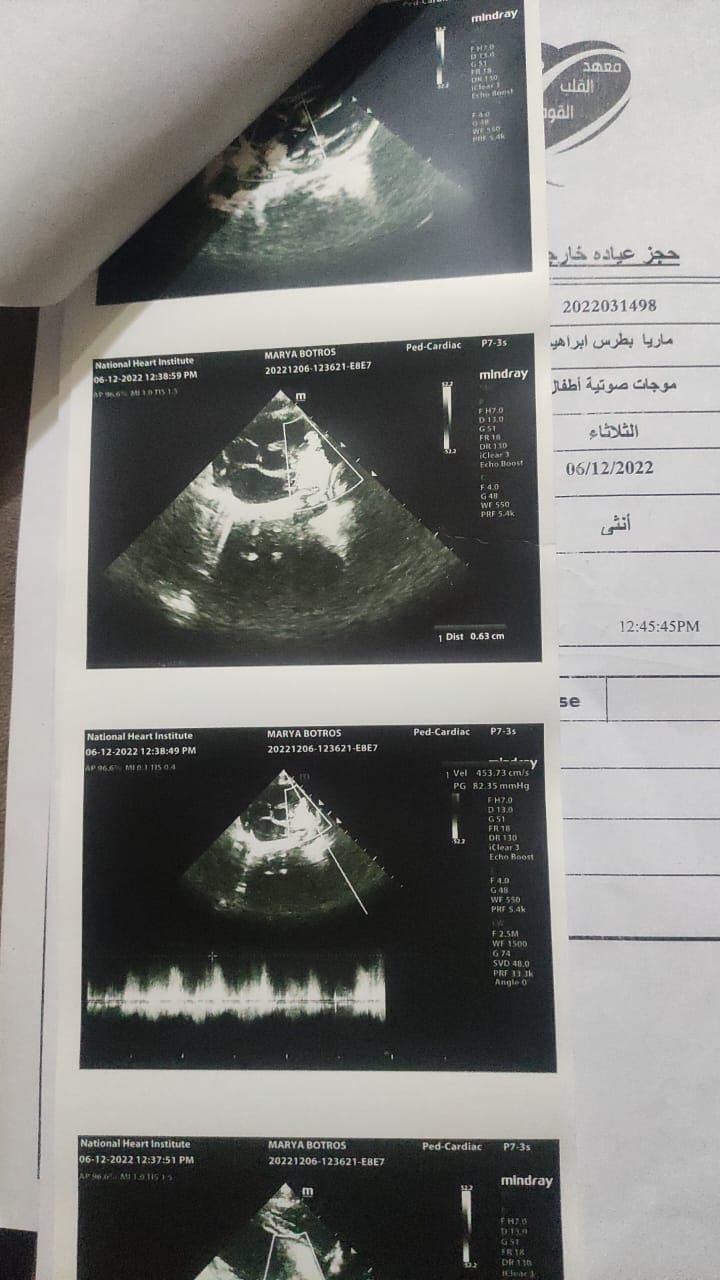

استغاث والدة الرضيعة ماريا بطرس، لإنقاذ ابنته المصابة بعيب خلقي في القلب، والتي تحتاج إلى قسطرة غير جراحية، لغلق وصلة شريانية بالقلب عن طريق سدادة.

وأضاف بطرس، أثناء فترة العلاج قام الأطباء بعمل الفحوصات للاطمئنان على صحة الطفلة، وعندها اكتشفوا أنها تعاني من عيب خلقي في القلب، وعندها أقر الأطباء في معهد القلب من ضرورة خضوع الطفلة لقسطرة غير جراحية، باستخدام جهاز وصلة شريانية وسدادة لعلاج هذا العيب الخلقي، وذلك وفقًا لتقرير طبي صدر يوم 1 من ديسمبر 2022.